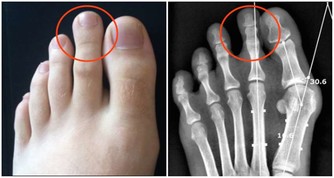

酒精的主要成分是乙醇,主要是是通過人體肝臟代謝。

乙醇在乙醇脫氫酶的作用下產生乙醛,乙醛在乙醛脫氫酶的作用下產生乙酸和水,

乙酸進入三羧酸循環生成二氧化碳和水。

而喝酒臉紅正是因為體內缺乏將乙醛轉化為乙酸的酶,

導致乙醛在體內蓄積,損害肝臟功能,增加肝病風險,長期飲酒也會導致食道癌的發生。